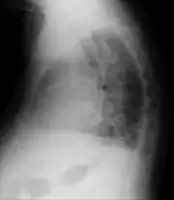

| Pulmonary edema with small pleural effusions on both sides. | |

Low oxygen saturation and disturbed arterial blood gas readings support the proposed diagnosis by suggesting a pulmonary shunt. A chest X-ray will show fluid in the alveolar walls, Kerley B lines, increased vascular shadowing in a classical batwing peri-hilum pattern, upper lobe diversion (increased blood flow to the superior parts of the lung), and possibly pleural effusions. In contrast, patchy alveolar infiltrates are more typically associated with noncardiogenic edema[8]